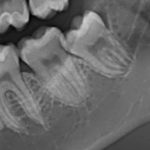

Questo protocollo operativo è stato denominato Tecnica Colorimetrica. Essa si avvale di una sostanza colorante e rivelatrice dei batteri presenti sui denti i quali vengono evidenziati con un colore che può essere viola/rosso per la placca batterica che è presente sui denti da meno di 24 ore, blu invece per i batteri che sono presenti da più di 24 ore.

La visualizzazione dei batteri adesi ai denti dei nostri pazienti permette di far vedere o di vedere che cosa sia la placca, dove essa si trovi ed è di fondamentale aiuto nella sua completa rimozione.

“Rimuovi il colore ed avrai i tuoi denti puliti!” è il principio da insegnare a noi stessi ed ai nostri amici pazienti al fine ottenere, finalmente, un risultato ottimale, ricordandoci sempre che in una bocca pulita non vi è mai malattia parodontale.